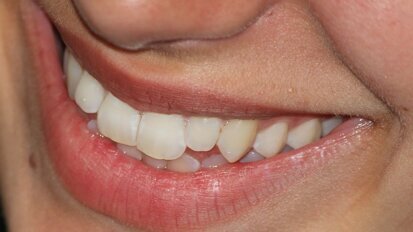

Cyfrowe techniki projektowania w estetycznych ostatecznych uzupełnieniach implantoprotetycznych

W artykule opisano wykorzystanie pozycjonomera – szablonu nazębnego do ustalenia prawidłowej angulacji wszczepu wykonanego na podstawie skanu ...

zapisz